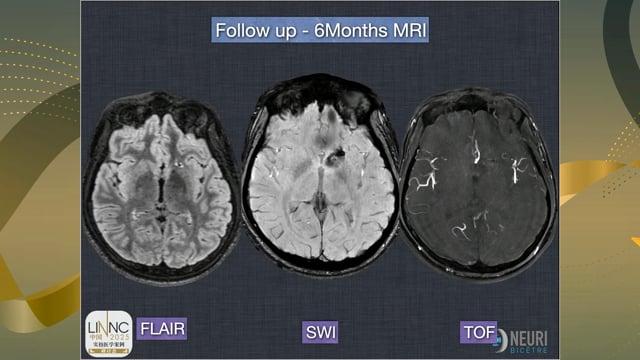

«Catch» the displacement of the WEB!

AneurysmsIntrasacular devices

May 28, 2025